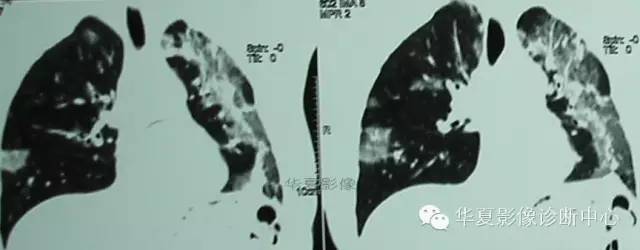

CT图像特点:双侧胸膜下片状、蜂窝状改变,肺内长条索状影向胸膜延伸。

结果:慢性嗜酸细胞性肺炎

胸部X片显示不呈段或叶性分布的周围片状阴影,常为双侧分布。糖皮质激素治疗后48h内症状和胸片可迅速消失。在同一局部可反复发生,数年后变为纤维化或蜂窝状改变。 糖皮质激素治疗效果显著,常可恢复正常,因停药较易复发,故全疗程需在一年以上。

补充病例:

2006/04/24

2006/05/22